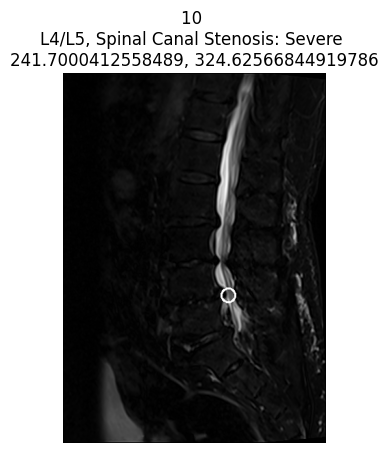

Hàm hiển thị vị trí tổn thương trên ảnh

def display_coor_on_img(c, i, title):

center_coordinates = (int(c['x']), int(c['y']))

radius = 10

color = (255, 0, 0) # Màu đỏ BGR

thickness = 2

IMG = i['dicom'].pixel_array

IMG_normalized = cv2.normalize(IMG, None, alpha=0, beta=255, norm_type=cv2.NORM_MINMAX, dtype=cv2.CV_8U)

IMG_with_circle = cv2.circle(IMG_normalized.copy(), center_coordinates, radius, color, thickness)

IMG_with_circle = cv2.cvtColor(IMG_with_circle, cv2.COLOR_BGR2RGB)

plt.imshow(IMG_with_circle)

plt.axis('off')

plt.title(title)

plt.show()- Vẽ một vòng tròn đỏ lên vị trí tổn thương trên ảnh MRI (theo tọa độ x, y đã gán nhãn).

- Hiển thị lên màn hình với tiêu đề tùy ý.

coor_entries = df_coor[df_coor['study_id'] == int(patient['study_id'])]

print("Chỉ hiển thị các trường hợp nặng (Severe) cho bệnh nhân này")

for idc, c in coor_entries.iterrows():

for i in im_list_dcm[str(c['series_id'])]['images']:

if int(i['SOPInstanceUID']) == int(c['instance_number']):

try:

patient_severity = patient[

f"{c['condition'].lower().replace(' ', '_')}_{c['level'].lower().replace('/', '_')}"

]

except Exception as e:

patient_severity = "unknown severity"

title = f"{i['SOPInstanceUID']} \n{c['level']}, {c['condition']}: {patient_severity} \n{c['x']}, {c['y']}"

if patient_severity == 'Severe':

display_coor_on_img(c, i, title)

- Lọc ra tất cả các vùng tổn thương được gán nhãn cho bệnh nhân đang xét.

- Với mỗi vùng tổn thương, tìm ảnh MRI tương ứng (dựa trên

series_idvàinstance_number). - Kiểm tra mức độ tổn thương (severe hay không).

- Nếu là Severe, vẽ vòng tròn lên vị trí tổn thương và hiển thị ảnh.